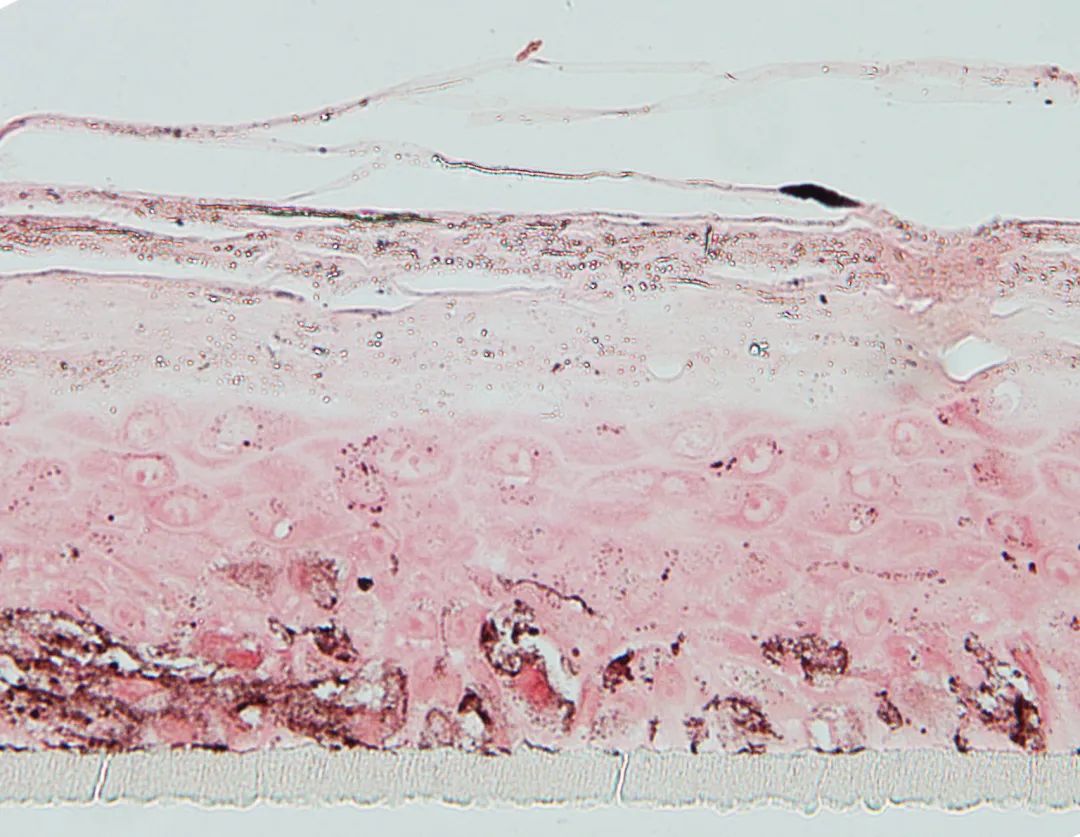

其中EpiKutis 是由中國人皮膚組織分離出的角質(zhì)形成細胞,在特定的培養(yǎng)環(huán)境下生成的活性組織(屬于組織工程技術(shù))。它與正常人體表皮高度類似,是具有典型的基底層、棘層、顆粒層及角質(zhì)層的表皮復層化結(jié)構(gòu)。

圖:EpiKutis 表皮模型,圖源博溪生物官網(wǎng)

EpiKutis 是目前國內(nèi)首款實現(xiàn)產(chǎn)業(yè)化生產(chǎn)的皮膚測試模型,也是皮膚生物學研究和化妝品體外功效性評價的一個有效工具。